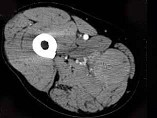

- 单项选择题男,30岁, 主诉右大腿肿块年余,逐渐增大, 局部胀痛及压痛,根据图像表现, 最可能的诊断是 ( )

D、横纹肌肉瘤